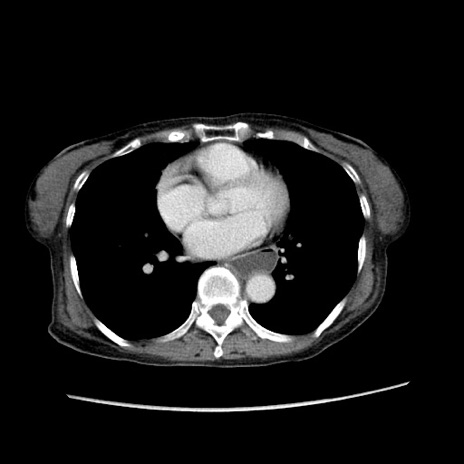

症例25(横断像)

【症例】80歳代女性

【主訴】胸のつかえ感

【現病歴】約9時間前に食後から胸のつかえた感じあり、嘔吐あり、来院。

【既往歴】胃癌(全摘)、胆摘、虫垂炎

【身体所見】心窩部に圧痛あり、反跳痛なし。

【データ】WBC 5700、CRP 0.05